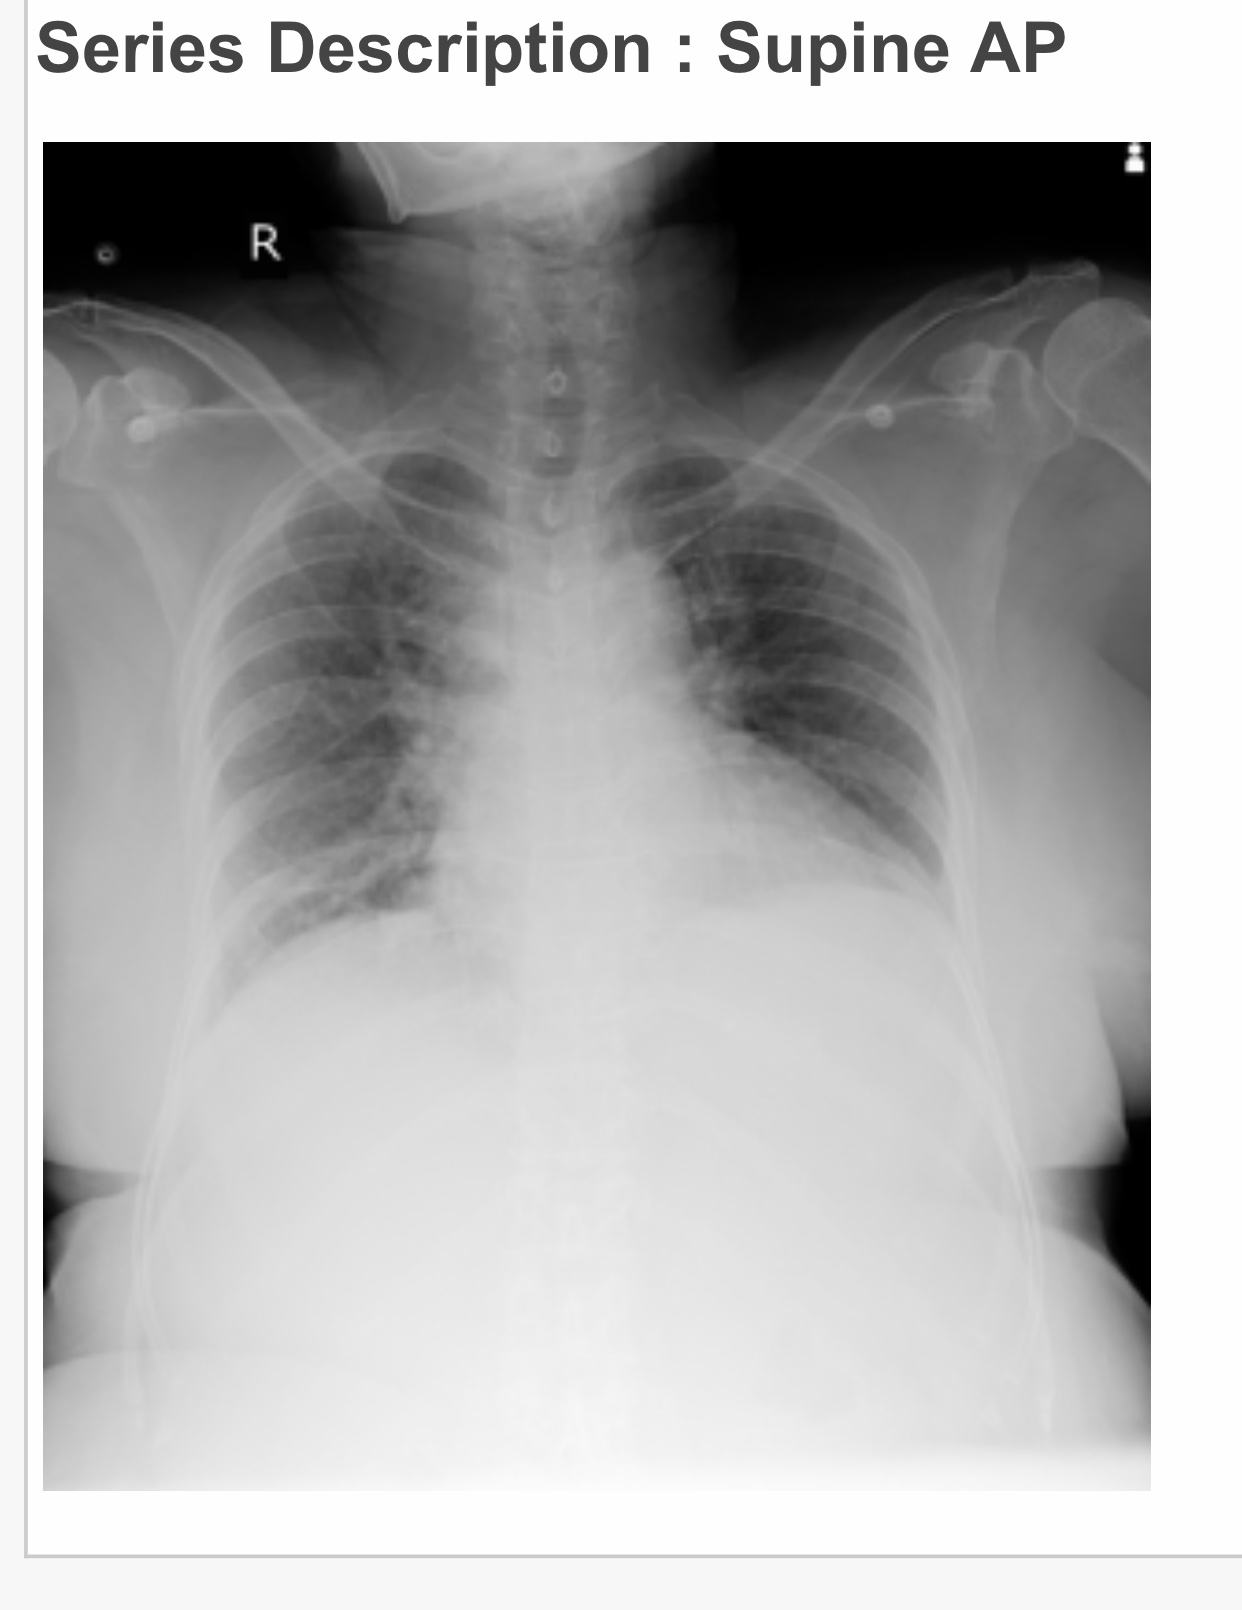

• CVS Examination:

Inspection-

Shape of chest-bilaterally symmetrical

Trachea-central in position

Jvp -raised

Apical impulse couldn't be seen.

Precordial and epigastric pulsations *absent

No visible scars,sinuses,engorged veins*

Palpation-

Apexbeat- couldn't be appreciated as pt is obese .

Parasternal heave,grade1 ,over left parasternal line

No palpable thrill ,no tenderness

Auscultation-

S1,s2 heard in pulmonary,mitral,tricuspid areas

Nomurmurs

•Respiratory Examination:

Normal vesicular breath sounds,

Bilateral air entry present

Trachea - central

Wheeze - absent

Crepts + bilaterally in isa ,iaa,inter scapular and mammary areas